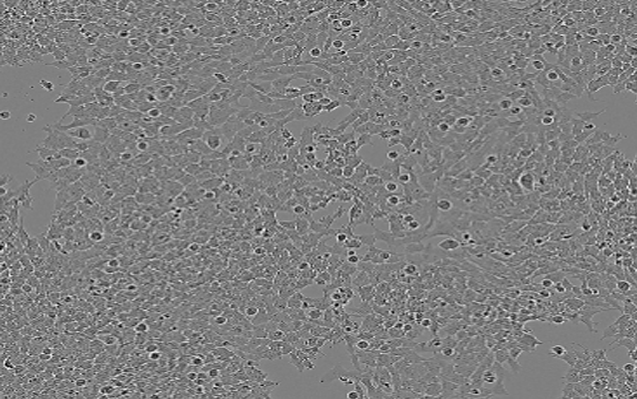

SJSA-1;人骨肉瘤细胞

D283 Med;人脑髓母细胞瘤细胞

MDA-MB-361;人乳腺癌细胞

H4;人神经胶质瘤细胞

SK-N-MC;人神经上皮瘤细胞

SK-N-AS;人脑神经母细胞瘤细胞

Daoy;人脑髓母细胞瘤细胞

DU4475;人乳腺上皮细胞

BT-20;人乳腺癌细胞

VIEW MORE